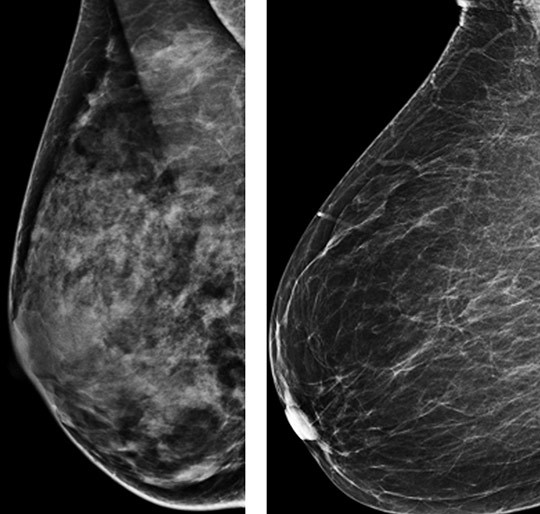

Illustrasjonsfoto: Ap/Scanpix

Høy mammografisk tetthet kan maskere svulster og redusere sensitiviteten ved mammografiscreening. Bruk av andre bildeundesøkelser i tillegg til mammografi er vist å øke deteksjonsraten. Hvordan brystkreftrisiko og mammografisk tetthet er assosiert med diagnose av infiltrerende brystkreft innen 12 måneder etter mammografi (intervallkreft), er nå undersøkt i en prospektiv kohortstudie i USA (1).

Rundt halvparten av kvinnene hadde mammografisk tette bryst. For disse var risikoen for intervallkreft lav etter negativt screeningresultat og lav fem års brystkreftrisiko. Kvinner med ekstremt tette bryst og middels eller høy fem års brystkreftrisiko, og de med heterogen brysttetthet og høy eller svært høy fem års risiko, hadde høy risiko for å utvikle intervallkreft (> 1 tilfelle/1 000 mammografiundersøkelser).